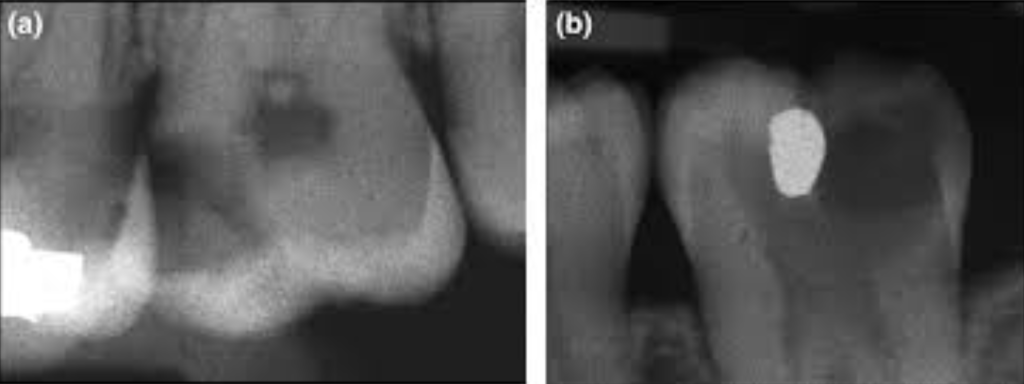

dentinal bridge formation radiograph

Cas Clinique 2 — L’exposition iatrogène en cours de préparation

Présentation : Mme Benali, 34 ans, en bonne santé générale, se présente pour une restauration de la 25 cariée. Lors de la préparation à la fraise, le praticien crée une effraction pulpaire de 0,3 mm, ponctiforme. Saignement minime et rapidement contrôlé en moins de 2 minutes avec boulette de coton stérile. La digue est en place depuis le début.

Problématique identifiée : Exposition pulpaire iatrogène minime (< 0,5 mm) sur pulpe saine, en conditions aseptiques, patient sans antécédent général. Indication possible de coiffage direct si les conditions sont réunies.

Prise en charge : Vérification de l’hémostase complète (saignement arrêté < 2 min : bon pronostic). Désinfection au NaOCl 2,5 %, rinçage sérum physiologique, séchage doux. Application de MTA ProRoot® sur le site d’exposition et la dentine environnante. Attente de début de prise (20 min sous coton humide). Obturation coronaire définitive en composite résine en deux temps.

Évolution attendue : Contrôle à 3 semaines : absence de symptômes. À 3 mois : radiographie montrant une ébauche de pont dentinaire. À 12 mois : pont dentinaire visible, absence de résorption interne, vitalité maintenue.

Point pédagogique : L’exposition iatrogène n’est pas une catastrophe si elle est immédiatement prise en charge dans les règles. L’hémostase rapide et les conditions aseptiques sont les deux critères déterminants du succès.